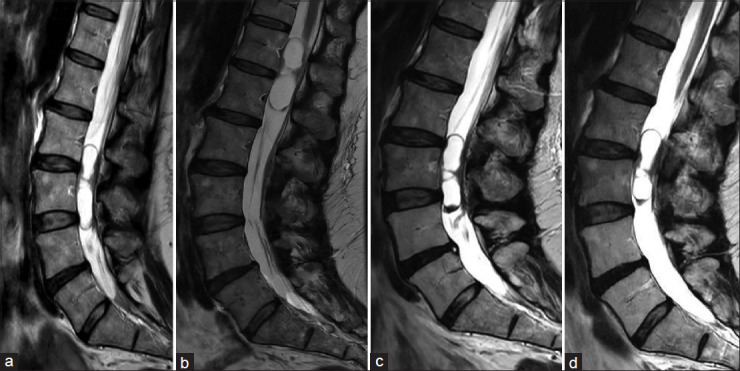

移动神经鞘瘤或雪旺细胞瘤是罕见的,但其在椎管内迁移的能力使诊断和治疗复杂化。我们报告两例下胸椎和腰椎的移动神经鞘瘤,均表现为间歇性腰痛和腿部疼痛以及腿部麻木。核磁共振成像显示囊性肿块随着时间的推移而改变位置,最终引起破坏性疼痛,促使手术干预。术后结果良好,突出了在术前计划中考虑肿瘤移动性的重要性。移动神经鞘瘤目前的诊断和手术挑战。认识到肿瘤移动的潜力对于制定有效的治疗策略至关重要,因为它影响临床表现和手术方法。

Mobile schwannomas, or schwann cell tumors, are rare, but their ability to migrate within the spinal canal complicates diagnosis and treatment. We report two cases of mobile schwannomas in the lower thoracic and lumbar spine, both presenting with intermittent low back and leg pain and leg numbness. MRIs revealed cystic masses that shifted positions over time, eventually causing disruptive pain that prompted surgical intervention. Postoperative outcomes were favorable, highlighting the importance of considering tumor mobility in preoperative planning. Mobile schwannomas present diagnostic and surgical challenges. Recognizing the potential for tumor mobility is crucial in developing effective treatment strategies, as it impacts clinical presentation and surgical approach.